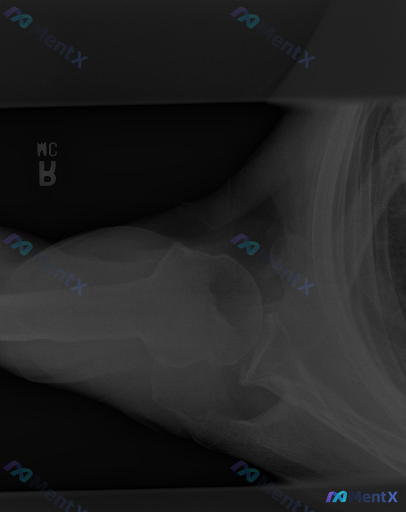

网上看到一份右肩关节腋位的X线影像资料和结构化分析,有点意思——

影像报告的结论很明确:

- 肱骨近端、肩胛带骨骼结构完整,皮质连续,无骨折透亮线

- 腋位下肱骨头与肩胛盂对合良好,无脱位/半脱位

- 关节间隙正常,无明显骨赘、钙化或软组织肿胀

总体印象:未见明显影像学异常

但问题是,假设这个病例是有临床症状的(比如肩痛、活动受限),这种“片子没事但人不舒服”的情况其实很常见。